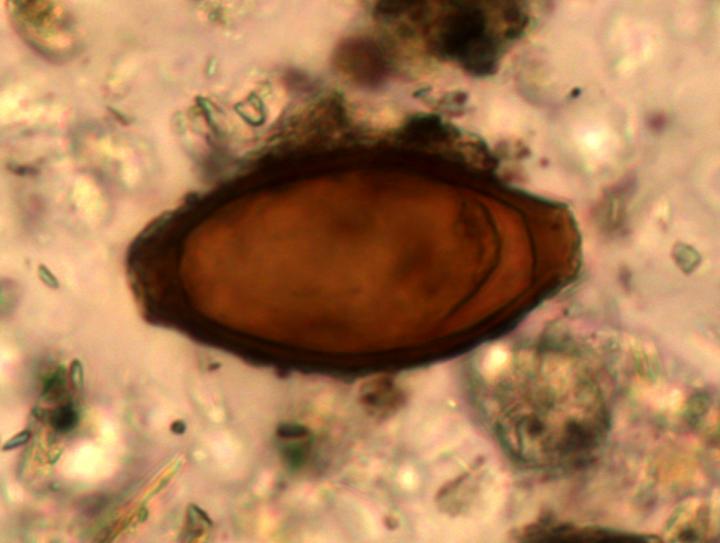

However, new archaeological research has revealed that -- for all their apparently hygienic innovations -- intestinal parasites such as whipworm, roundworm and Entamoeba histolytica dysentery did not decrease as expected in Roman times compared with the preceding Iron Age, they gradually increased.

Dr Piers Mitchell brought together evidence of parasites in ancient latrines, human burials and 'coprolites' -- or fossilised faeces -- as well as in combs and textiles from numerous Roman Period excavations across the Roman Empire.